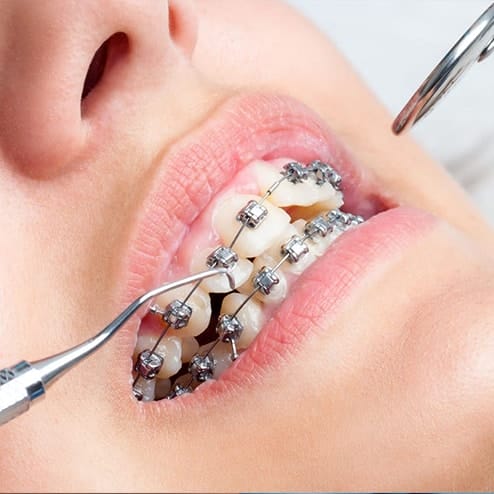

Chỉnh nha

Navii Dental Care đã điều trị cho gần 1000 khách hàng gặp các vấn đề lệch lạc về răng và khớp cắn trở nên CHUẨN KHỚP CẮN – RĂNG ĐỀU ĐẸP – CUNG RĂNG TRÒN. Với phương pháp thẩm mỹ không cần phẫu thuật này, bạn không chỉ “lột xác” về bên ngoài mà còn cải thiện khả năng ăn nhai và phát âm.